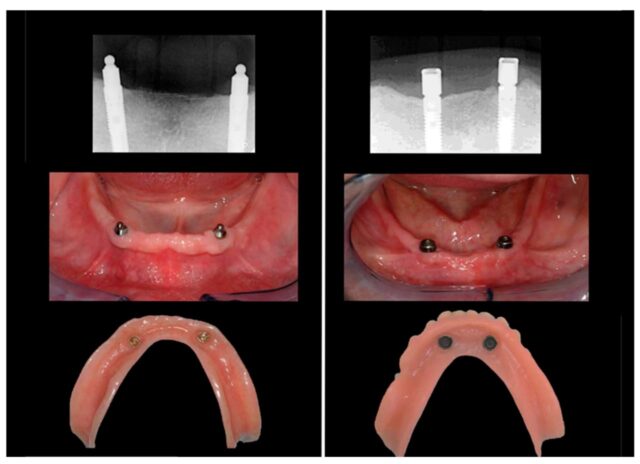

A. Implant-Retained Overdenture

Denture rests on gum but is retained by implants for better hold.

Commonly 2–4 implants in mandible or 4–6 in maxilla.

Denture can “snap” onto attachments.

1. Ball and socket